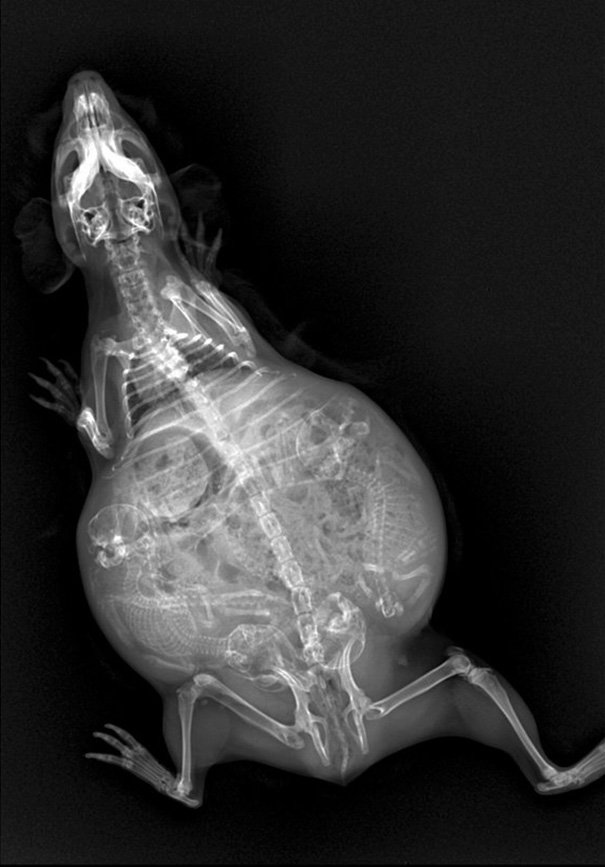

морская свинка